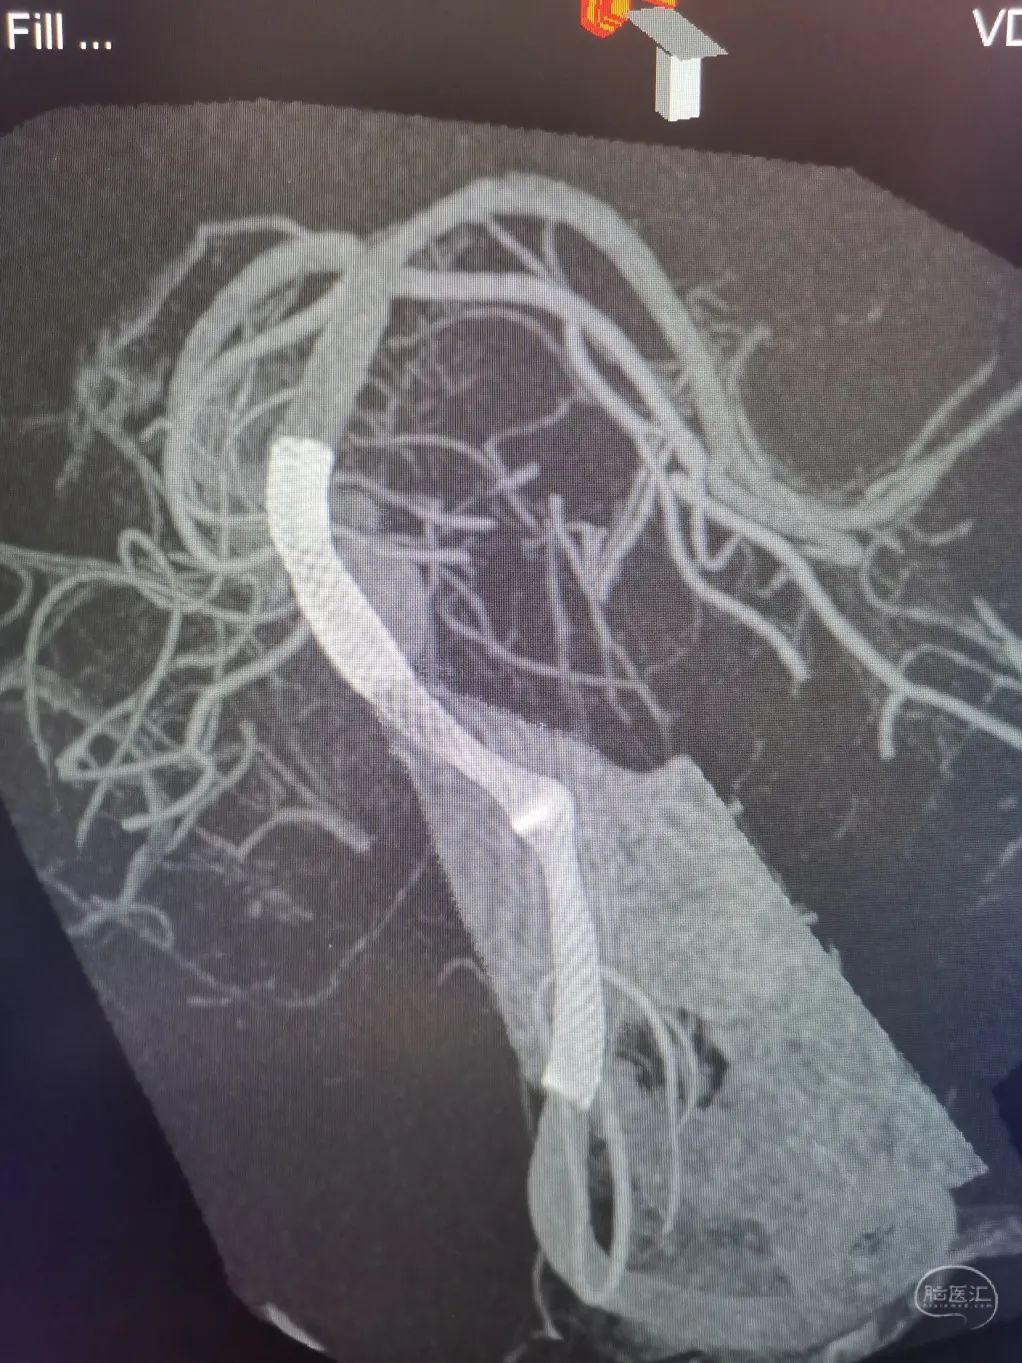

3D重建显示基底动脉下部、双椎结合部、左椎多发夹层动脉瘤:

双抗5天后行左侧椎动脉多发夹层动脉瘤Pipeline™ Flex 血流导向密网支架植入术。

Pipeline™ Flex 血流导向密网支架 PED-325-35

将Phenom™ 27微导管超选进入左侧大脑后动脉内,释放一枚3.25×35mm Pipeline™ Flex血流导向密网支架,远端定位在动脉瘤以远7mm,在动脉瘤处推密,近端定位在PICA起始部上端或远端,支架打开顺利。导引导管内推注替罗非班12mL,支架导管及微导管常规按摩,促进支架贴壁。

术后造影显示动脉瘤内造影剂滞留明显,载瘤动脉通畅。

支架CT: